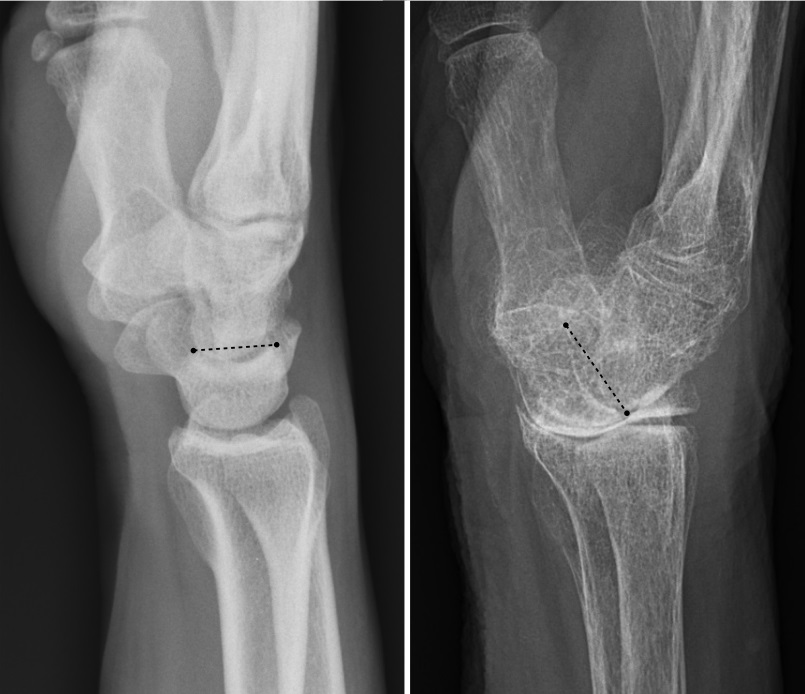

원위 요척 관절은 전완을 구성하는 요골과 척골의 원위 끝단 사이에 위치한 돌림 관절이다. 척골 머리와 요골의 척골 절흔에 의해 형성된 원위 요척 관절은 요골과 척골 경상 돌기 사이에 놓인 관절원판에 의해 요골-손목 관절로부터 분리된다. 원위 요척 관절은 근위 요척 관절(팔꿈치에서)과 함께 엎침과 뒤침을 가능하게 한다.[5]요골-손목 관절은 근위부의 요골과 관절원판, 그리고 원위부의 손목뼈 근위 열에 의해 형성된 타원 관절이다. 의학 용어 및 해부학 용어로는 요골수근관절이라고 한다.[25] 척골 쪽의 손목뼈는 간헐적으로 근위 측과 접촉한다. 즉, 세모뼈는 척골 편위 동안에만 접촉한다. 요골-손목 관절을 형성하는 부분은 위쪽의 요골의 아래쪽 끝과 관절원판의 아래쪽 면, 그리고 아래쪽의 손배뼈, 반달뼈, 세모뼈이다. 요골의 관절면과 관절원판의 아래쪽 면은 함께 가로로 타원형의 오목면을 형성하며, 이를 수용강이라 한다. 손배뼈, 반달뼈, 세모뼈의 위쪽 관절면은 매끄러운 볼록면을 형성하며, 이 볼록면을 과라고 하며 오목면에 들어간다.[7]

손목 통증은 수근관 증후군[16], 결절종[19], 힘줄염[20], 골관절염 등 여러 가지 원인으로 발생한다. 팔렌 검사와 같은 검사에는 손목의 손바닥 굽힘이 포함된다.류마티스 관절염과 같은 일부 질환에서는 손목에서 손이 벗어날 수 있다.

'손목 골절'은 일반적으로 원위 요골의 골절을 의미한다.

손목 통증은 수근관 증후군,[16] 결절종,[19] 힘줄염,[20] 및 골관절염 등 여러 가지 원인으로 인해 발생할 수 있다. 팔렌 검사와 같은 검사는 손목의 손바닥 굽힘을 유발하여 신경 압박 증상을 확인한다.류마티스 관절염과 같은 일부 질환에서는 손목에서 손이 벗어날 수 있다.